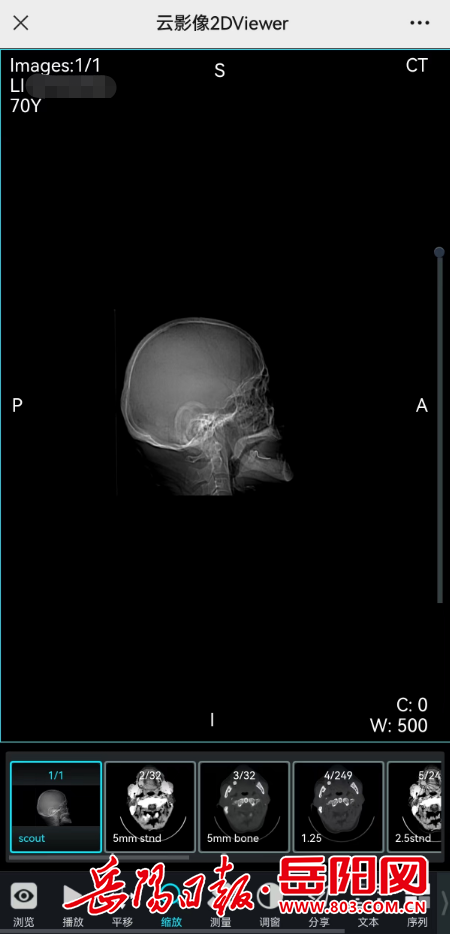

通常一次CT、MR检查有几百上千张图像,患者拿到传统的打印胶片通常只是病灶比较关键的几幅图像,而云胶片保存患者的全部原始影像资料,医生可清楚查看CT薄层,并具备窗宽窗位调整、动态展示、多维成像等多项影像浏览功能,读片效果更好,诊断更精准。

第三步:在跳转的报告单界面选择查看原始影像

第四步:选择后即可查看到报告原始影像